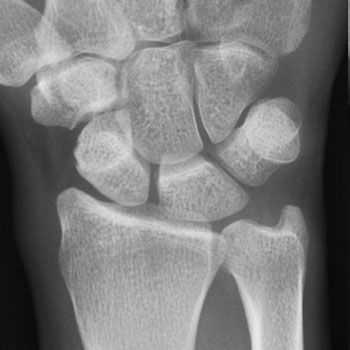

- Для подтверждения диагноза болезнь де Кервена может потребоваться рентген. На полученных снимках можно заметить наличие кальциноза в области первого костно-фиброзного канала;